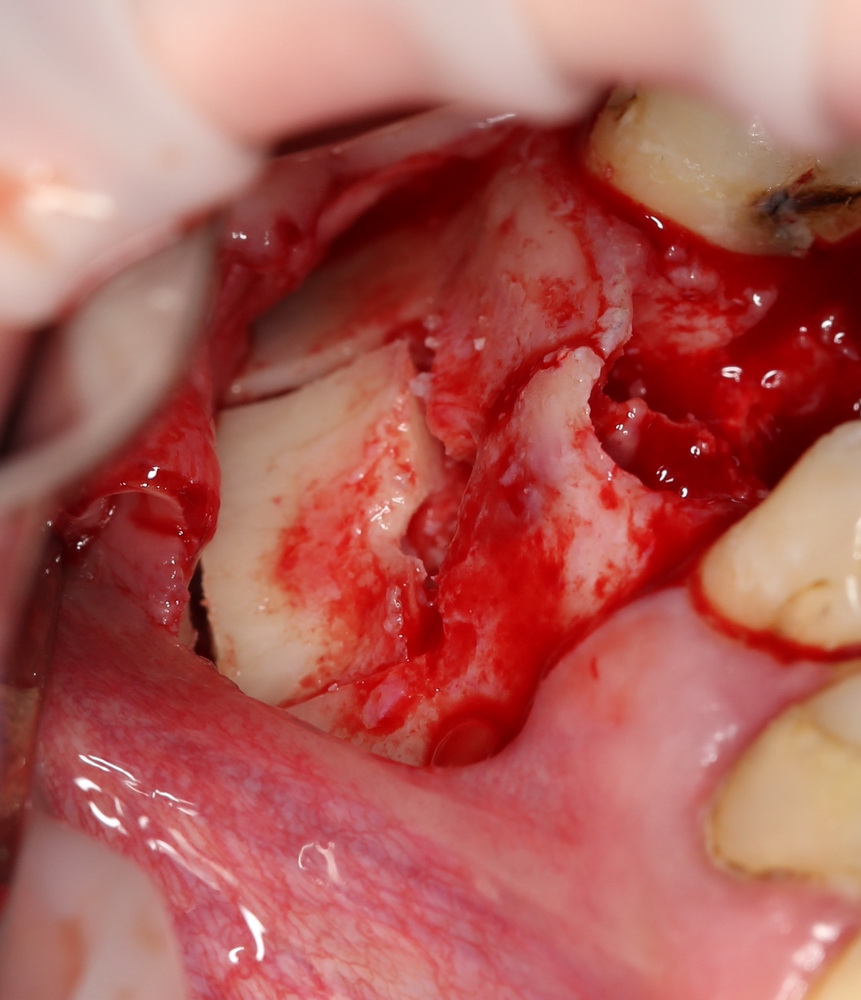

Синуслифтинг, удаление зуба и немедленная имплантация

Согласно современным представлениям об имплантологическом лечении, наиболее желательной является немедленная имплантация, т. е. установка импланта одномоментно с удалением зуба. Именно таким образом достигается быстрый эстетичный и функциональный результат, поскольку в данном случае мы практически не сталкиваемся с проблемой атрофии костной ткани и слизистой оболочки.

При наличии соответствующих условий возможно проведение операции немедленной имплантации одновременно с синуслифтингом (рис 54, 55, 56):

Рисунок 54, 55, 56. Проведение операции синуслифтинга одномоментно с удалением зуба и установкой импланта.

В ходе воспалительного процесса, при излишне травматичном удалении или вследствие анатомических особенностей нередко отсутствует вестибулярная стенка лунки зуба – в дальнейшем, это может привести неблагоприятному эстетическому и функциональному результату. Костный фрагмент, получившийся при создании доступа в верхнечелюстную полость, можно использовать для пластики внешней стенки лунки (рис 57, 58, 59):

Рисунок 57, 58, 59. Пластика внешней стенки лунки костным фрагментом при немедленной имплантации и синуслифтинге: слева – этап синуслифтинга и имплантации, в центре – пластика внешней стенки альвеолярного отростка методом аутотрансплантации костного фрагмента, справа – этап установки формирователей десны через 3 месяца после имплантации.